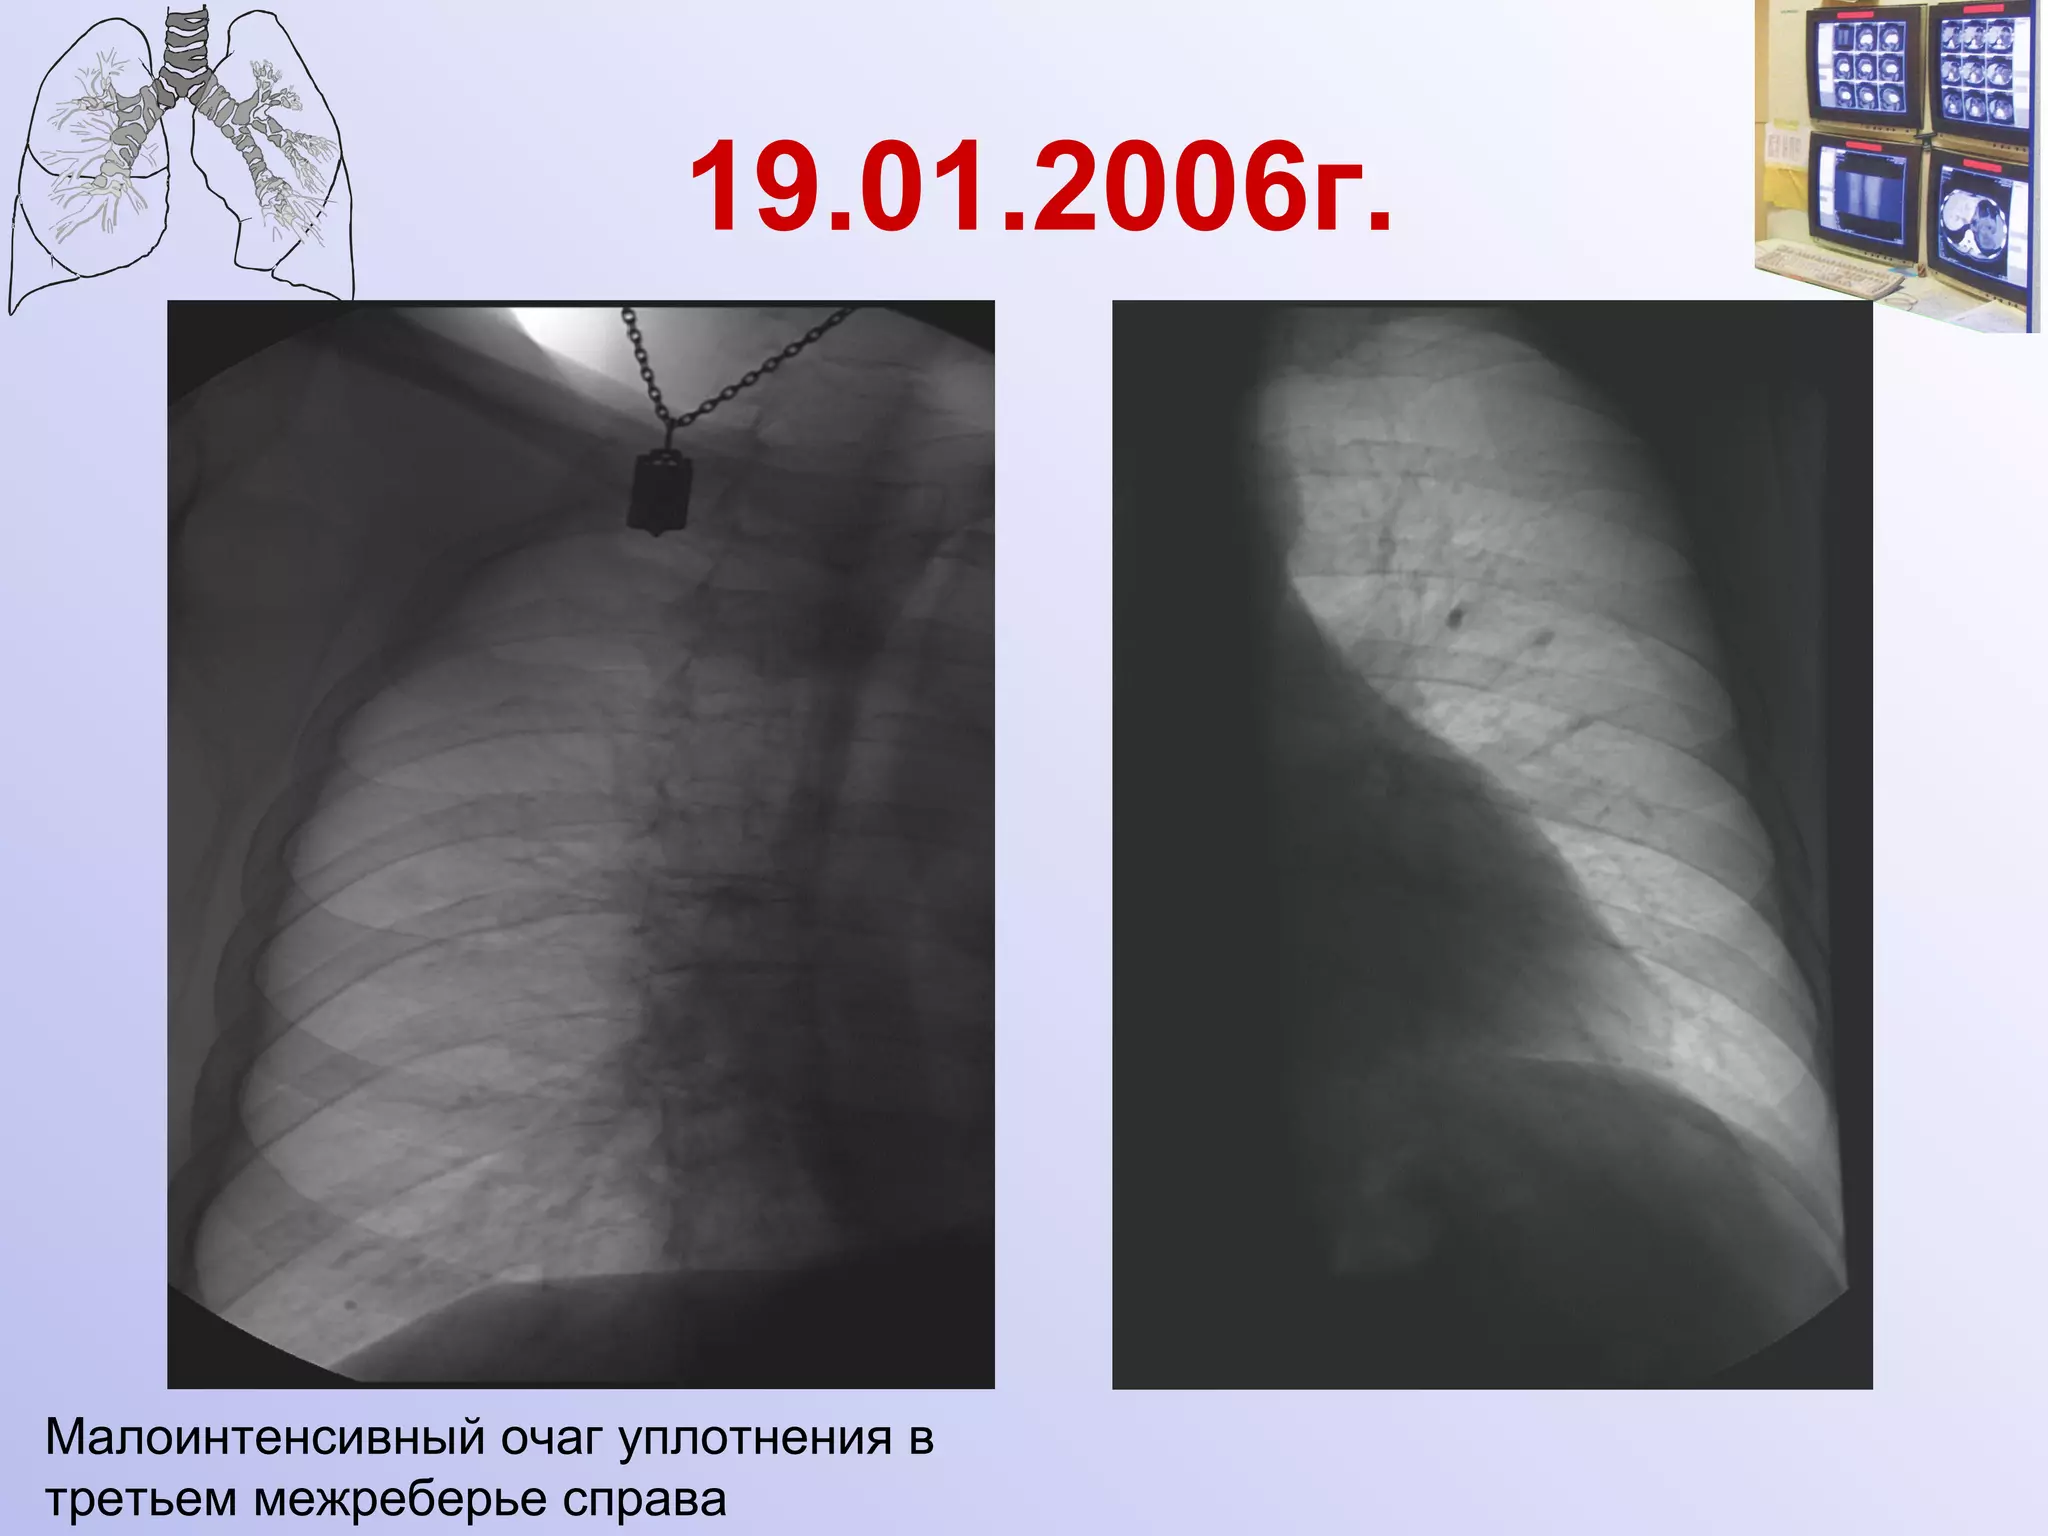

19.01.2006г.

19.01.2006г. Малоинтенсивный очаг уплотнения в третьем межреберье справа